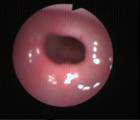

Acute Scrotum (Right scrotal Abscess)

Acute Scrotum